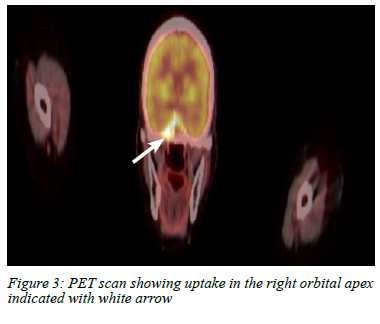

Full body positron emission tomography (PET) scan performed for staging purposes demonstrated the mass in the apex of the right orbit and superior aspect of the sphenoid sinus with no other areas of suspicious uptake (Figure 3). The patient was discussed at a multidisciplinary team (MDT) meeting where palliative radiotherapy to the metastatic site and a second-line aromatase inhibitor were proposed. She completed palliative whole brain radiotherapy with no resolution of symptoms. The patient is alive, but unfortunately remains blind in the right eye.

PET scan is used to identify other areas of metastases. In our patient the absence of other metastatic sites guided the MDT treatment decision to only administer palliative local therapy.

Blindness and ophthalmoplegia from breast cancer metastases to the orbital apex and sphenoid sinus after a 10-year disease-free interval is very rare. Involvement of the optic nerve differentiates this presentation from other forms of ophthalmoplegia found in the superior orbital fissure and cavernous sinus syndrome. A high-resolution CT scan is often sufficient to delineate the location and extent of the disease, and guide biopsy which is necessary to determine the aetiology and origin of the disease. A PET scan is used for oncological staging and to guide appropriate treatment. Prognosis for orbital metastasis of breast cancer is poor with an average survival of 31 months.4